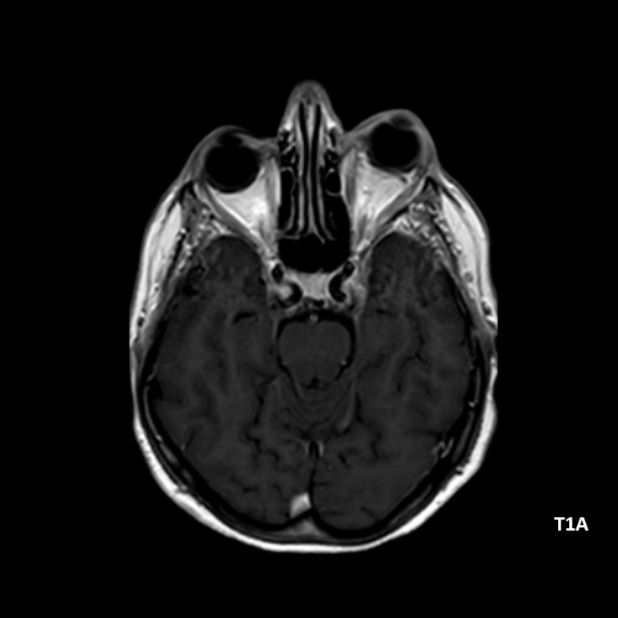

- A) Orbital MRG’de yağ baskılı T2A görüntülerde sol orbital globta ekzoftalmus (ok) izlenmiş olup retrobulbar yağlı dokuda kirlenmeler (ok) ve dilate superior oftalmik ven (ok) dikkati çekiyor. Beyin MRG’de kontrastlı T1A görüntüde sol kavernöz sinüste simetriğine oranla genişleme (ok) izleniyor.

- BT ve MRG: Propitozis, ekstraokuler kaslarda genişleme, superior oftalmik vende genişleme ve tortiyozite, ipsilateral kavernöz sinüste genişleme gösterilebilir. Serebral venöz konjesyonu olan ve intrakraniyal basınçları yükselen hastalarda serebral ödem, hemoraji, leptomeningeal ve kortikal venlerin dilastasyonunu görülebilir. Bunlara ek olarak travmaya sekonder olgularda BT ile eşlik eden fraktürler gösterilebilir.